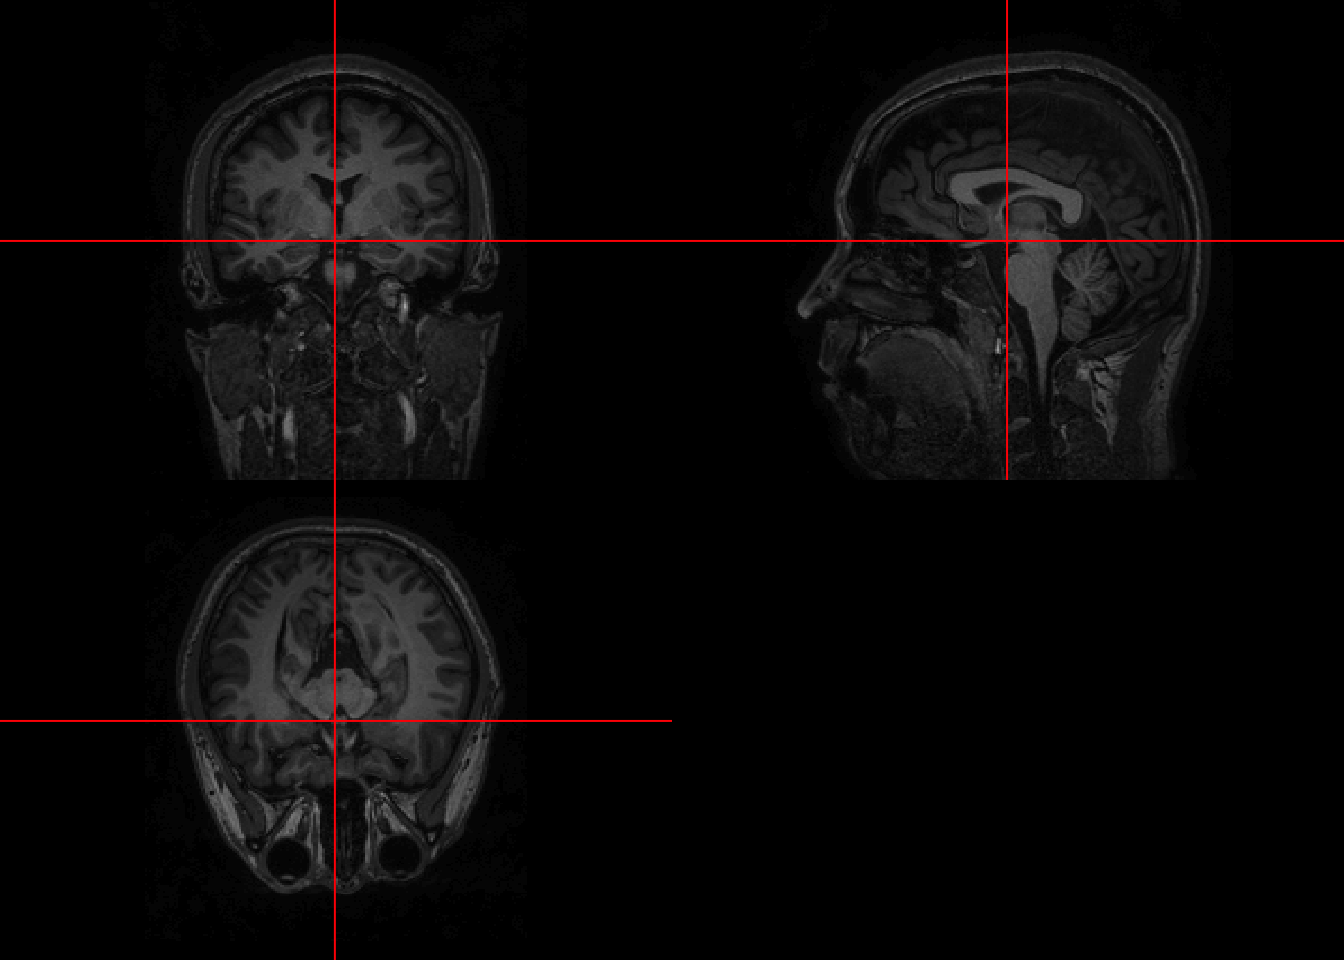

mask = readNIfTI(maskfpath, reorient=FALSE) 4.2 Visualization

This brain was collected with a bigger FOV than the previous scans. Thus a lot of body parts other than brain are shown.